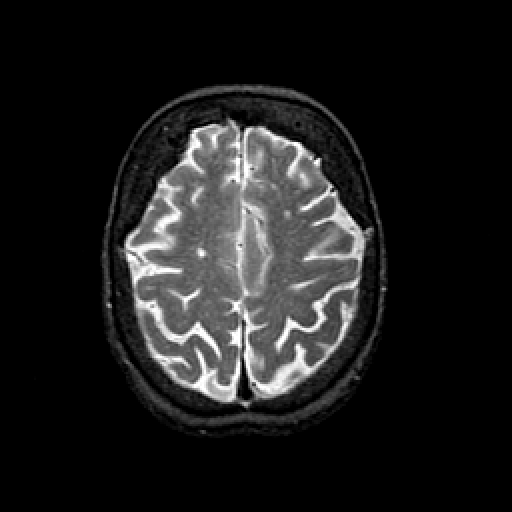

T2-weighted structural MR: Slice 40

Slice 40